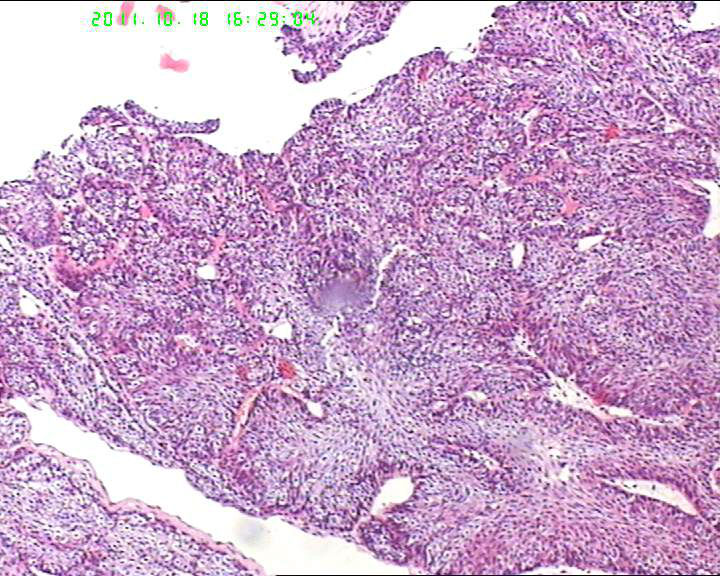

70岁女性体检发现膀胱肿物,是癌吗?

膀胱后壁一2*1cm大小肿物